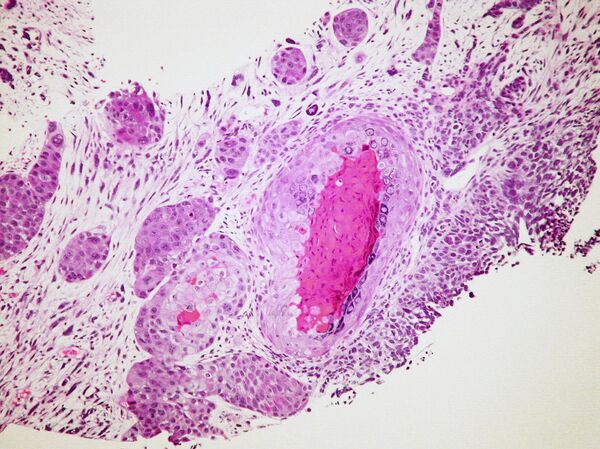

Día de lucha contra el cáncer

En otro orden, en el marco de este martes 4, Día Mundial de Lucha contra el Cáncer, la Organización Mundial de la Salud advirtió de un drástico aumento de casos.

Si la evolución actual se mantiene, dentro de veinte años habrá un 60 % más de diagnósticos en el mundo. La enfermedad afectará prácticamente a cada familia, puesto que una de cada cinco personas la padecerá.

De acuerdo al informe, la investigación permitió bajar el número de muertes, pero esta caída se ha producido sobre todo en los países ricos. Según estimaciones, estas naciones adoptaron programas de prevención que contribuyeron a reducir la tasa de mortalidad prematura en 20 %. En los países con ingresos bajos, la reducción sólo ha sido del 5%.